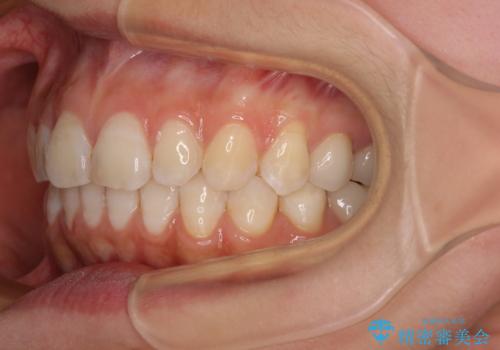

咬み合わせと目立っていた銀歯が改善され、患者様には大変満足していただきました。

- 下顎の前歯が隠れていることと、デコボコを気にして来院された患者様です。

銀歯やムシ歯処置の必要な歯が奥歯にあり気になっていたので、矯正治療の途中でセラミッククラウンへ変更し、その後歯列を仕上げていくこととしました。